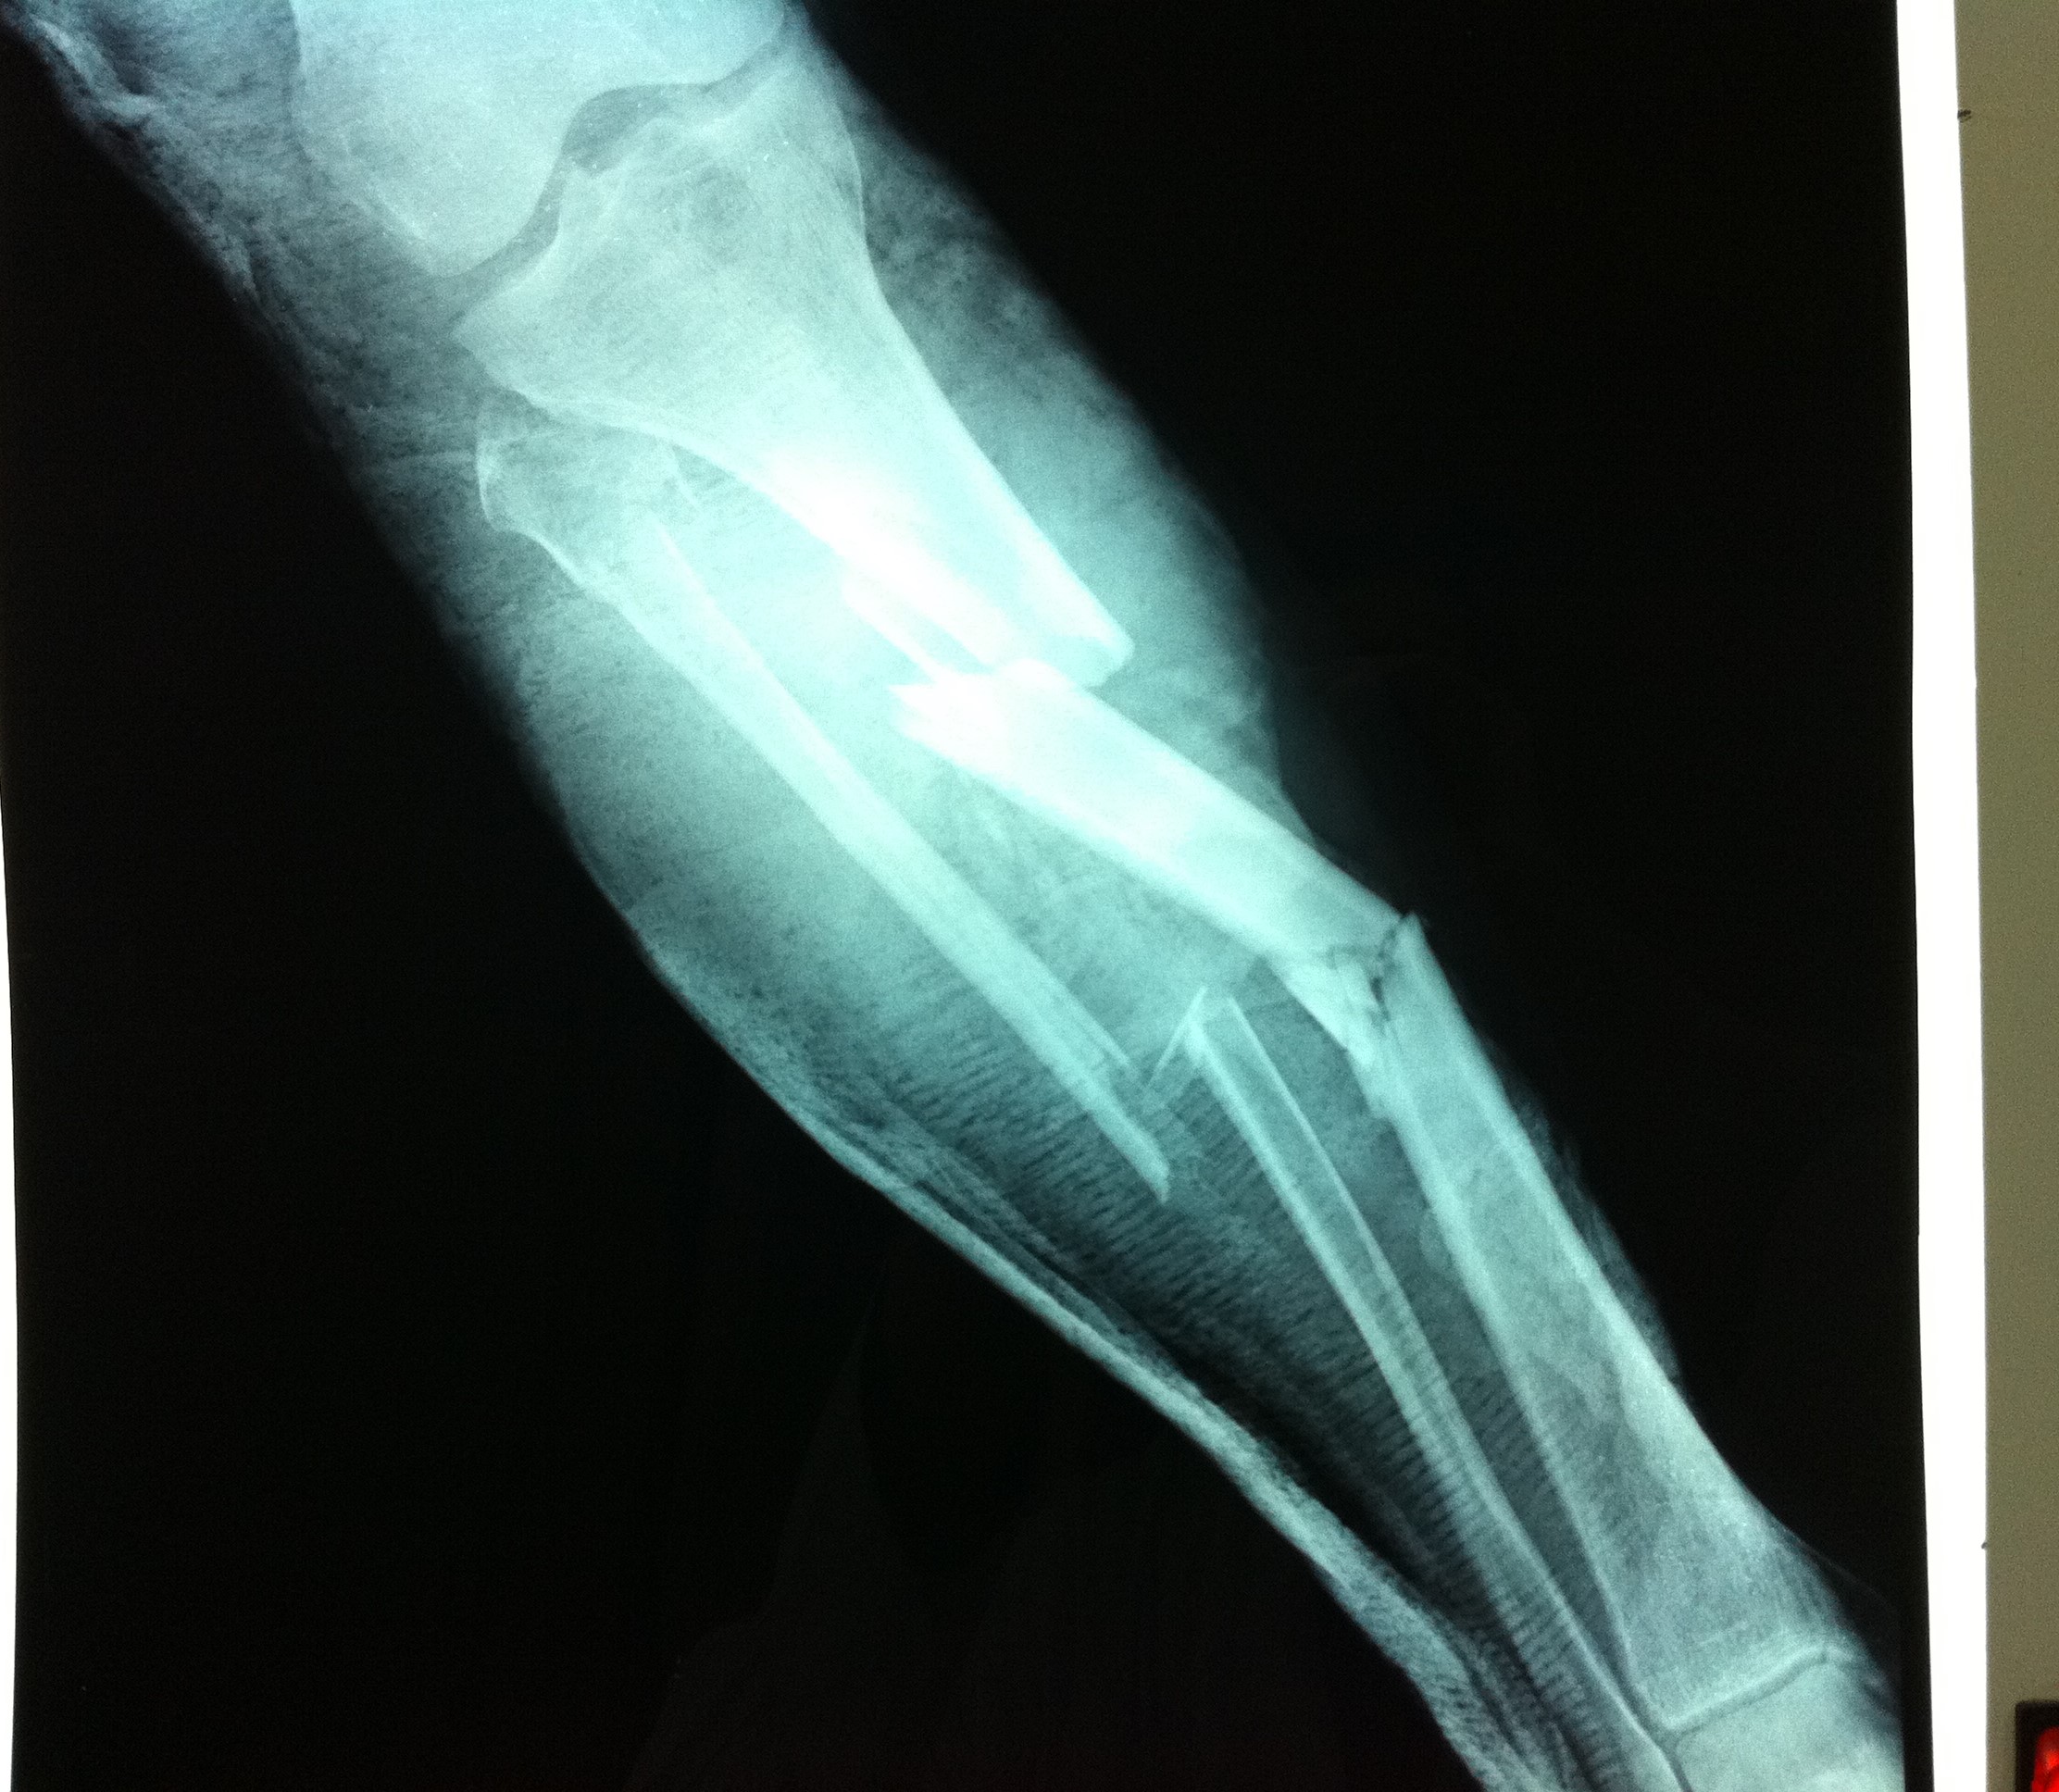

Από την άλλη, η χειρουργική μέθοδος που θα επιλεχθεί εξαρτάται από τον τύπο του κατάγματος, τις λοιπές συνοδές κακώσεις και την εμπειρία του χειρουργού. Ένα κάταγμα κνήμης μπορεί να αποκατασταθεί με τοποθέτηση ενδομυελικού ήλου, με ανοικτή ανάταξη και εσωτερική οστεοσύνθεση με πλάκες και βίδες ή με εξωτερική οστεοσύνθεση.